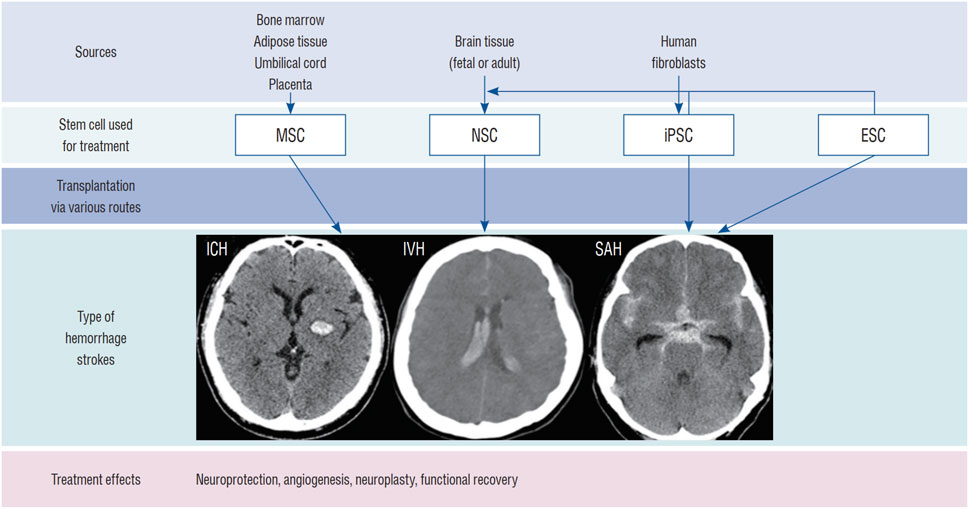

推進(jìn)腦出血的干細(xì)胞治療需要整合生物材料、基因工程和預(yù)處理策略以提升療效。盡管前景看好,但目前仍缺乏大規(guī)模、設(shè)計嚴(yán)謹(jǐn)?shù)哪X出血臨床試驗(yàn)和長期安全數(shù)據(jù)(圖3)。未來研究需著重優(yōu)化給藥途徑、劑量、時機(jī)以及符合藥品生產(chǎn)質(zhì)量管理規(guī)范的大規(guī)模細(xì)胞制備工藝。

圖3:用于治療ICH的干細(xì)胞類型:該圖顯示了用于治療ICH(腦實(shí)質(zhì)出血、腦室內(nèi)出血[IVH]和蛛網(wǎng)膜下腔出血[SAH])的干細(xì)胞類型,包括 NSC、間充質(zhì)干細(xì)胞 (MSC)、誘導(dǎo)多能干細(xì)胞 (iPSC) 和胚胎干細(xì)胞 (ESC)。